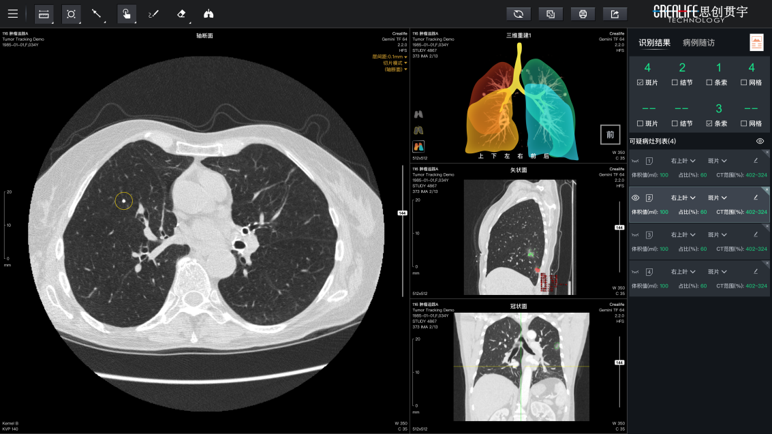

对于非血管通路的介入治疗,智能体同样发挥显著作用。以肺癌穿刺活检与消融为典型场景,智能体可基于多模态影像与深度学习算法实现肿瘤智能检测、多期随访及穿刺路径规划,有效提升病灶早期检出率与手术精准度。